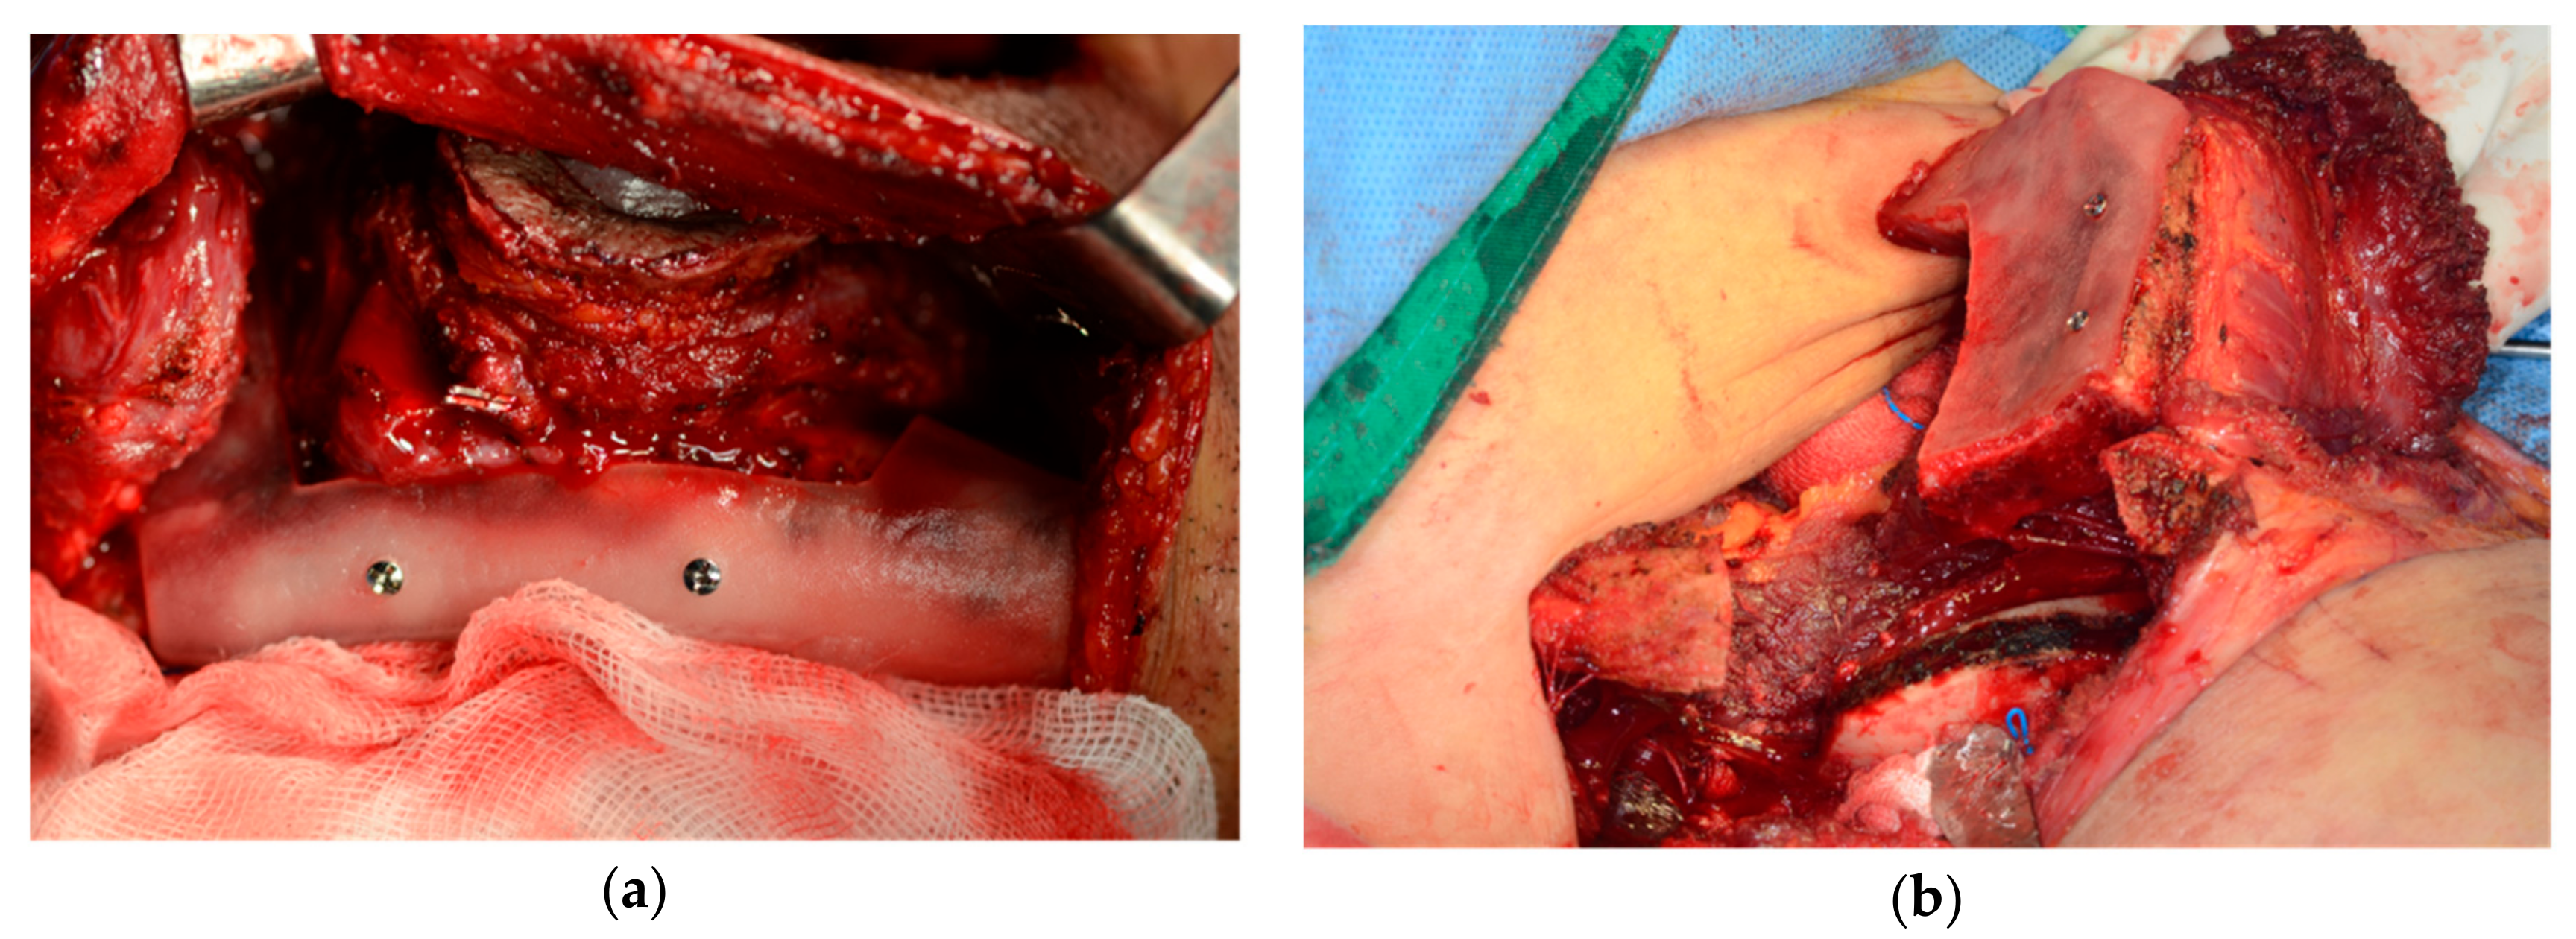

2.2. Surgical Technique